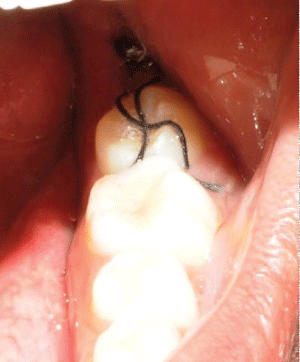

3- The tooth was inserted into the receiver socket and a "X" suture, using silk yarn, was made to keep it firm (Figure 6).

Figures 6: The tooth was inserted into the receiver socket and a "X" suture was made.